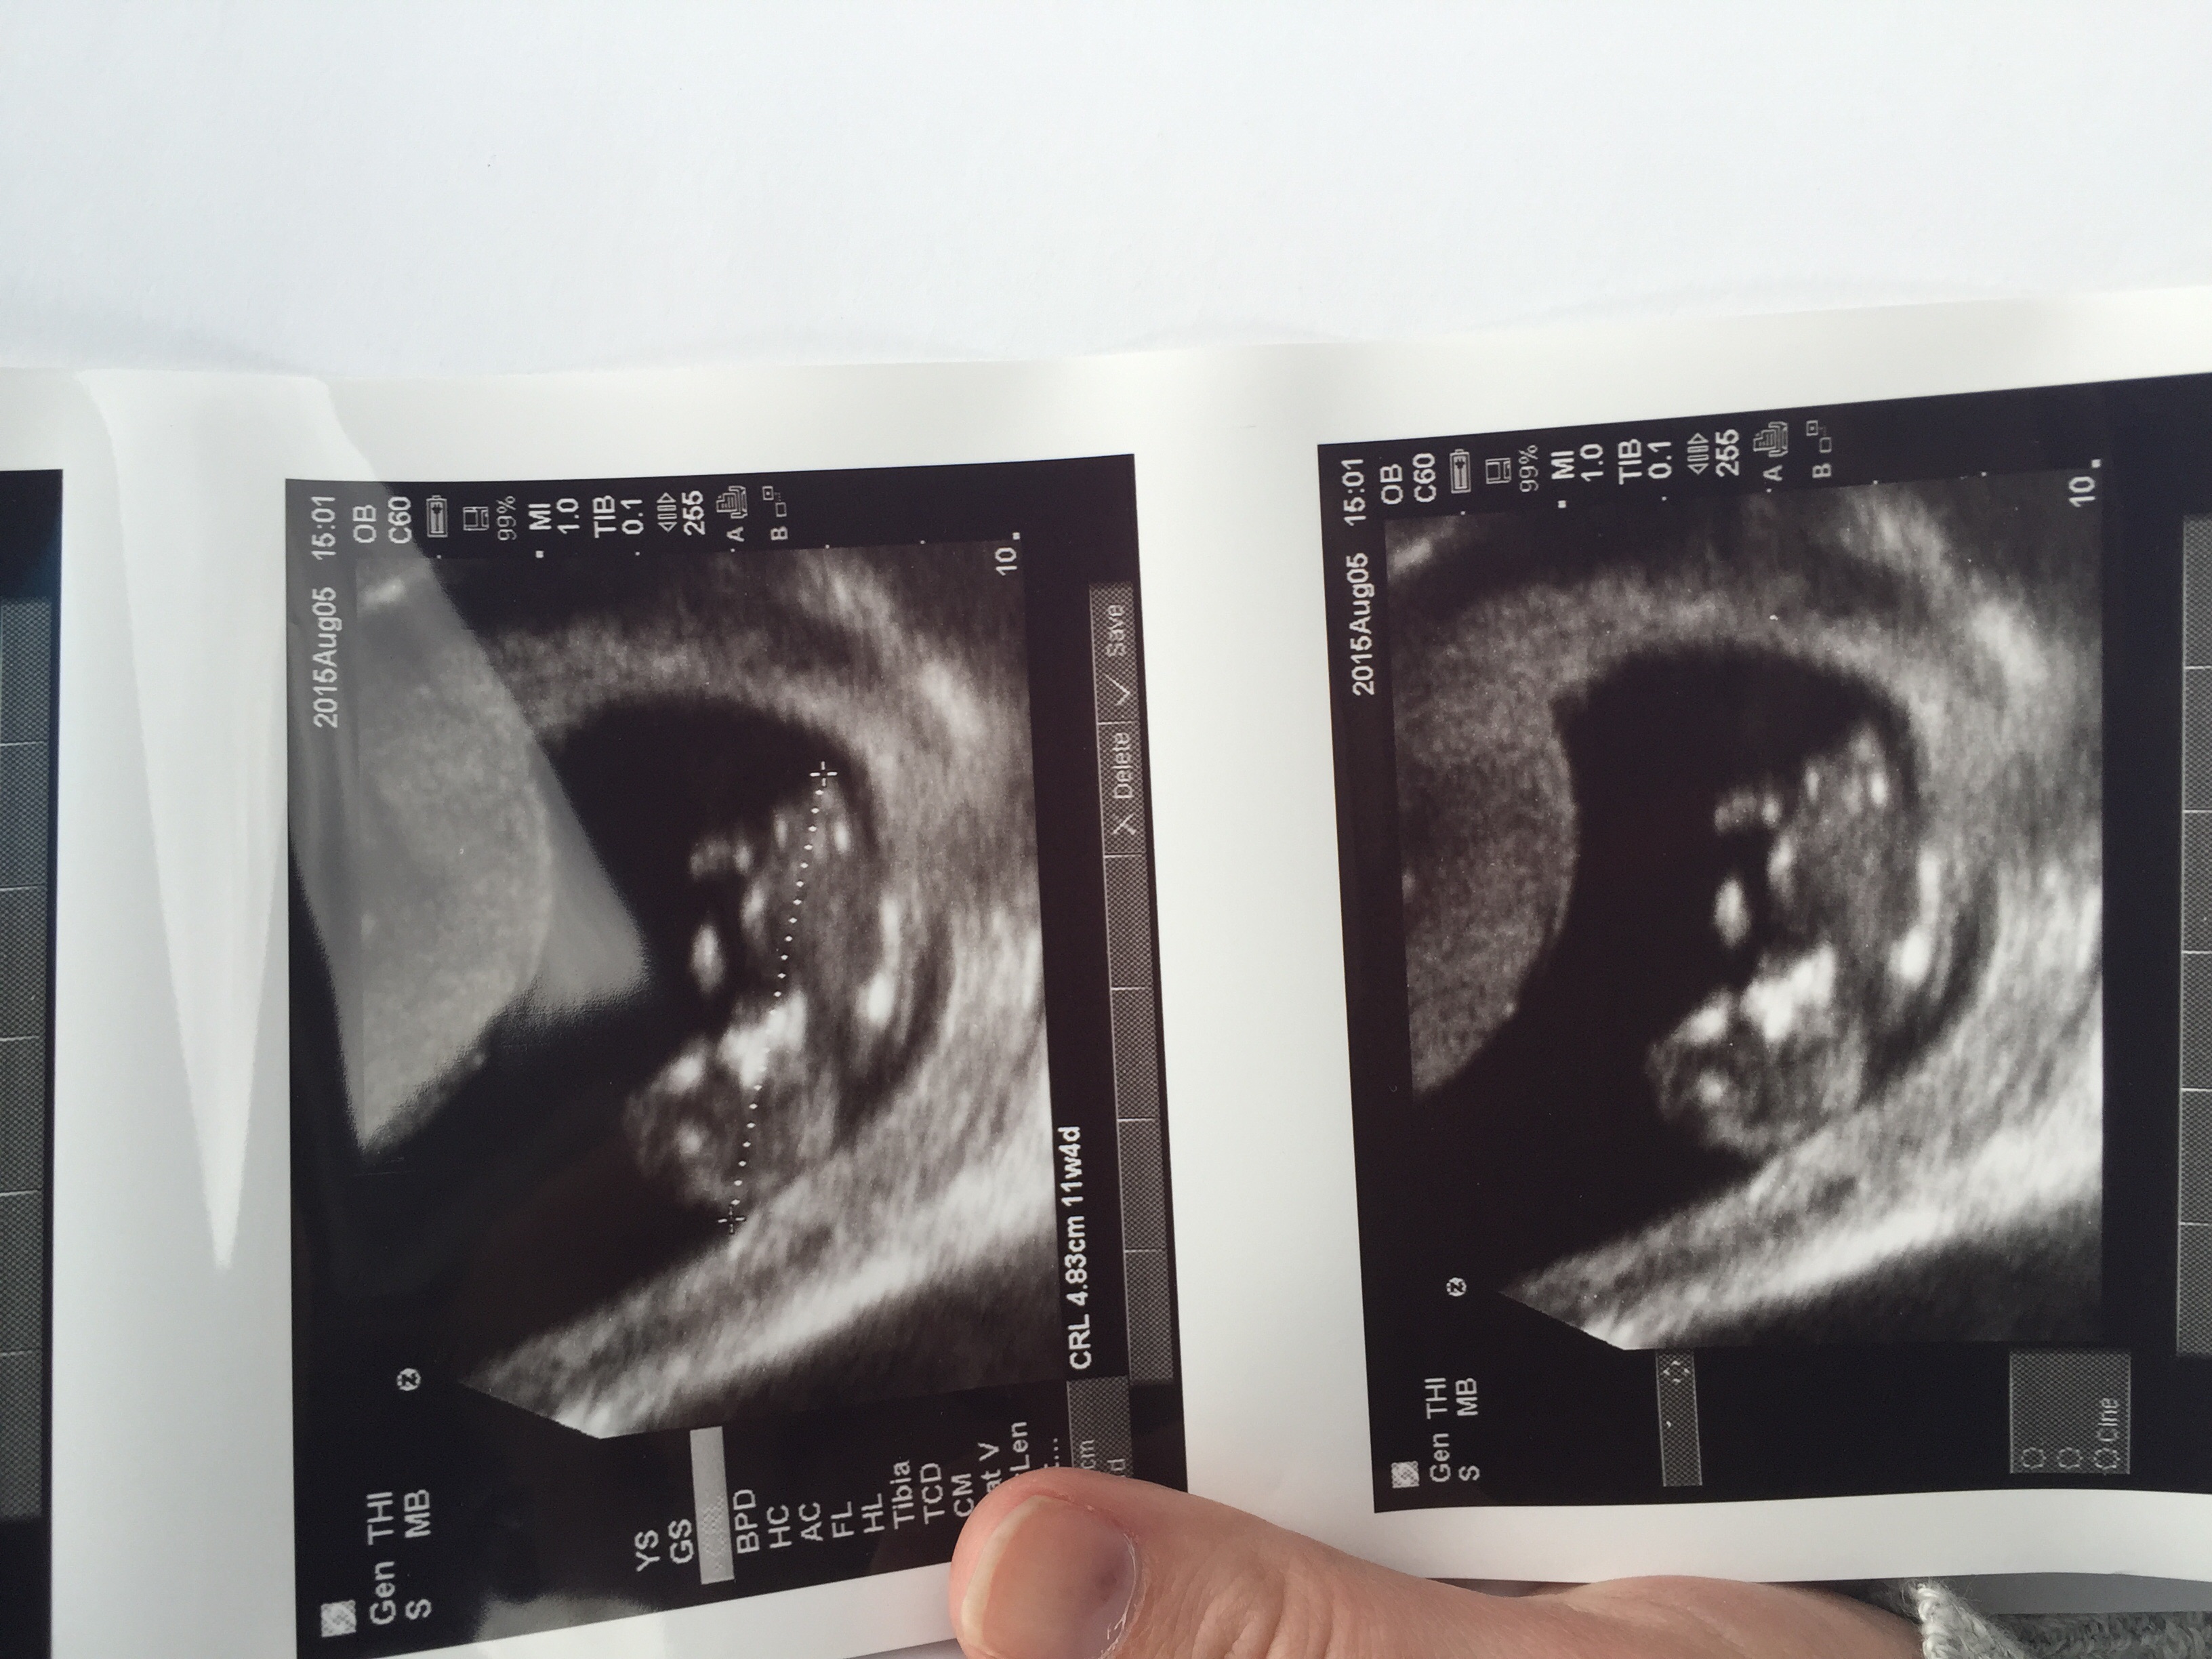

Here we are at 11 weeks 6 days. I will be 12 weeks tomorrow I had a big sono today and the tech did not say anything the whole time. She made me very nervous, especially because I did not get to hear the heartbeat and she kept poking my belly and seemed to be struggling to get the view she wanted. At the end she told me everything looked great so I was able to finally breathe.